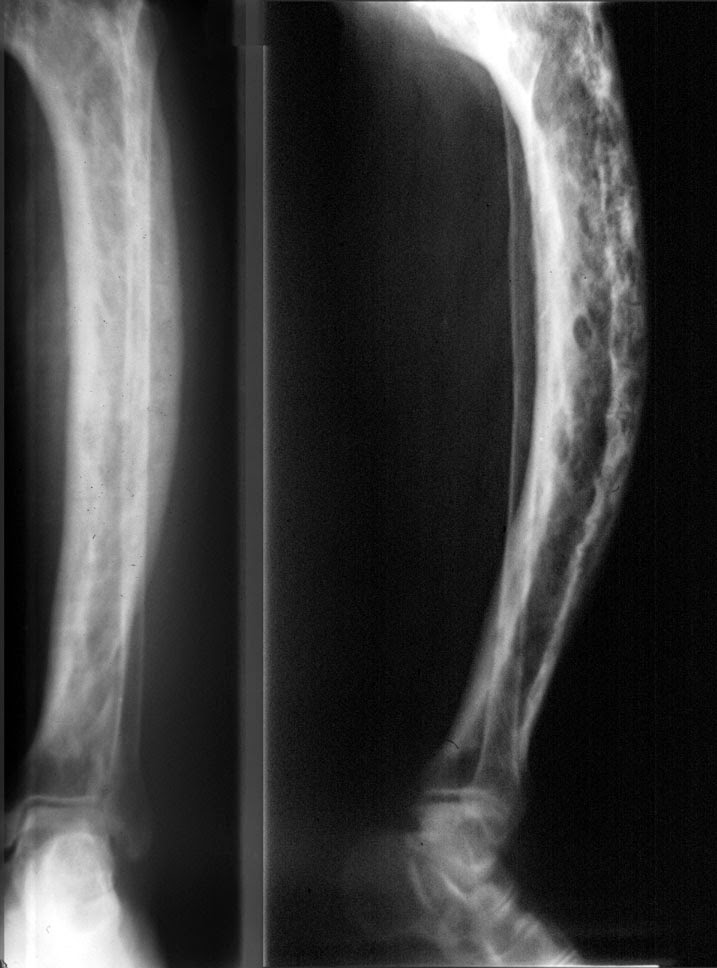

Daniel.OrtoSport Doença de PAGET dos ossos em estágio avançado fotos.

Νόσος του Paget των οστών με πόνο στα οστά, παραμόρφωση, οστεοπόρωση, οστεοαρθρίτιδα, κατάγματα